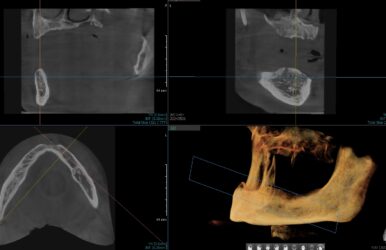

• I have never placed an immediate implant before but I think I found a good first case.

Patient is a 40 year male with a low smile line. Here is my proposed implant site.

I am planning on placing a 4.2×13 implant direct legacy 3. My current plan is to drill to a 2.8 osteotomy and then place the implant and hope for enough primary stability.